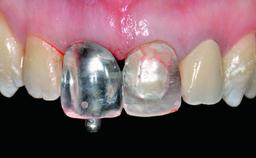

Replacement of a Missing Upper Left Central Incisor: Late Placement of an RC Bone Level Implant, CAD/CAM Zirconia Abutment

Abutment Type CAD/CAM

Prosthesis Type FDP

Retention Cemented, with prosthesis margin < 3mm submucosal Cemented, with prosthesis margin < 3mm submucosal